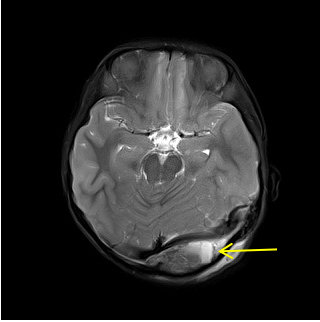

▲ 术前:左侧枕部硬膜外血肿

▲ 术前:血肿压迫横窦